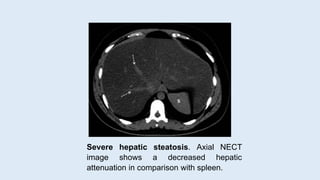

Severe hepatic steatosis. Axial NECT

image shows a decreased hepatic

attenuation in comparison with spleen.

 In the donor liver, moderate to severe steatosis (≥30% fat) is considered

unacceptably high and should be rejected for donation.